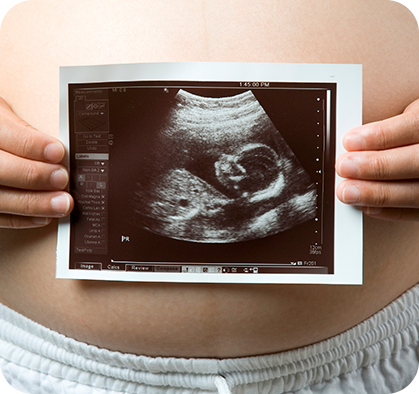

정밀 초음파 검사

임신 기간 동안 태아의 성장과 건강 상태를 확인하기 위해 정밀 초음파 검사가 진행될 수 있습니다.

중기 정밀 초음파 (21주 ~ 24주)

태아 주요 장기 구조를 확인하여 기형 여부를 확인하는 검사입니다.